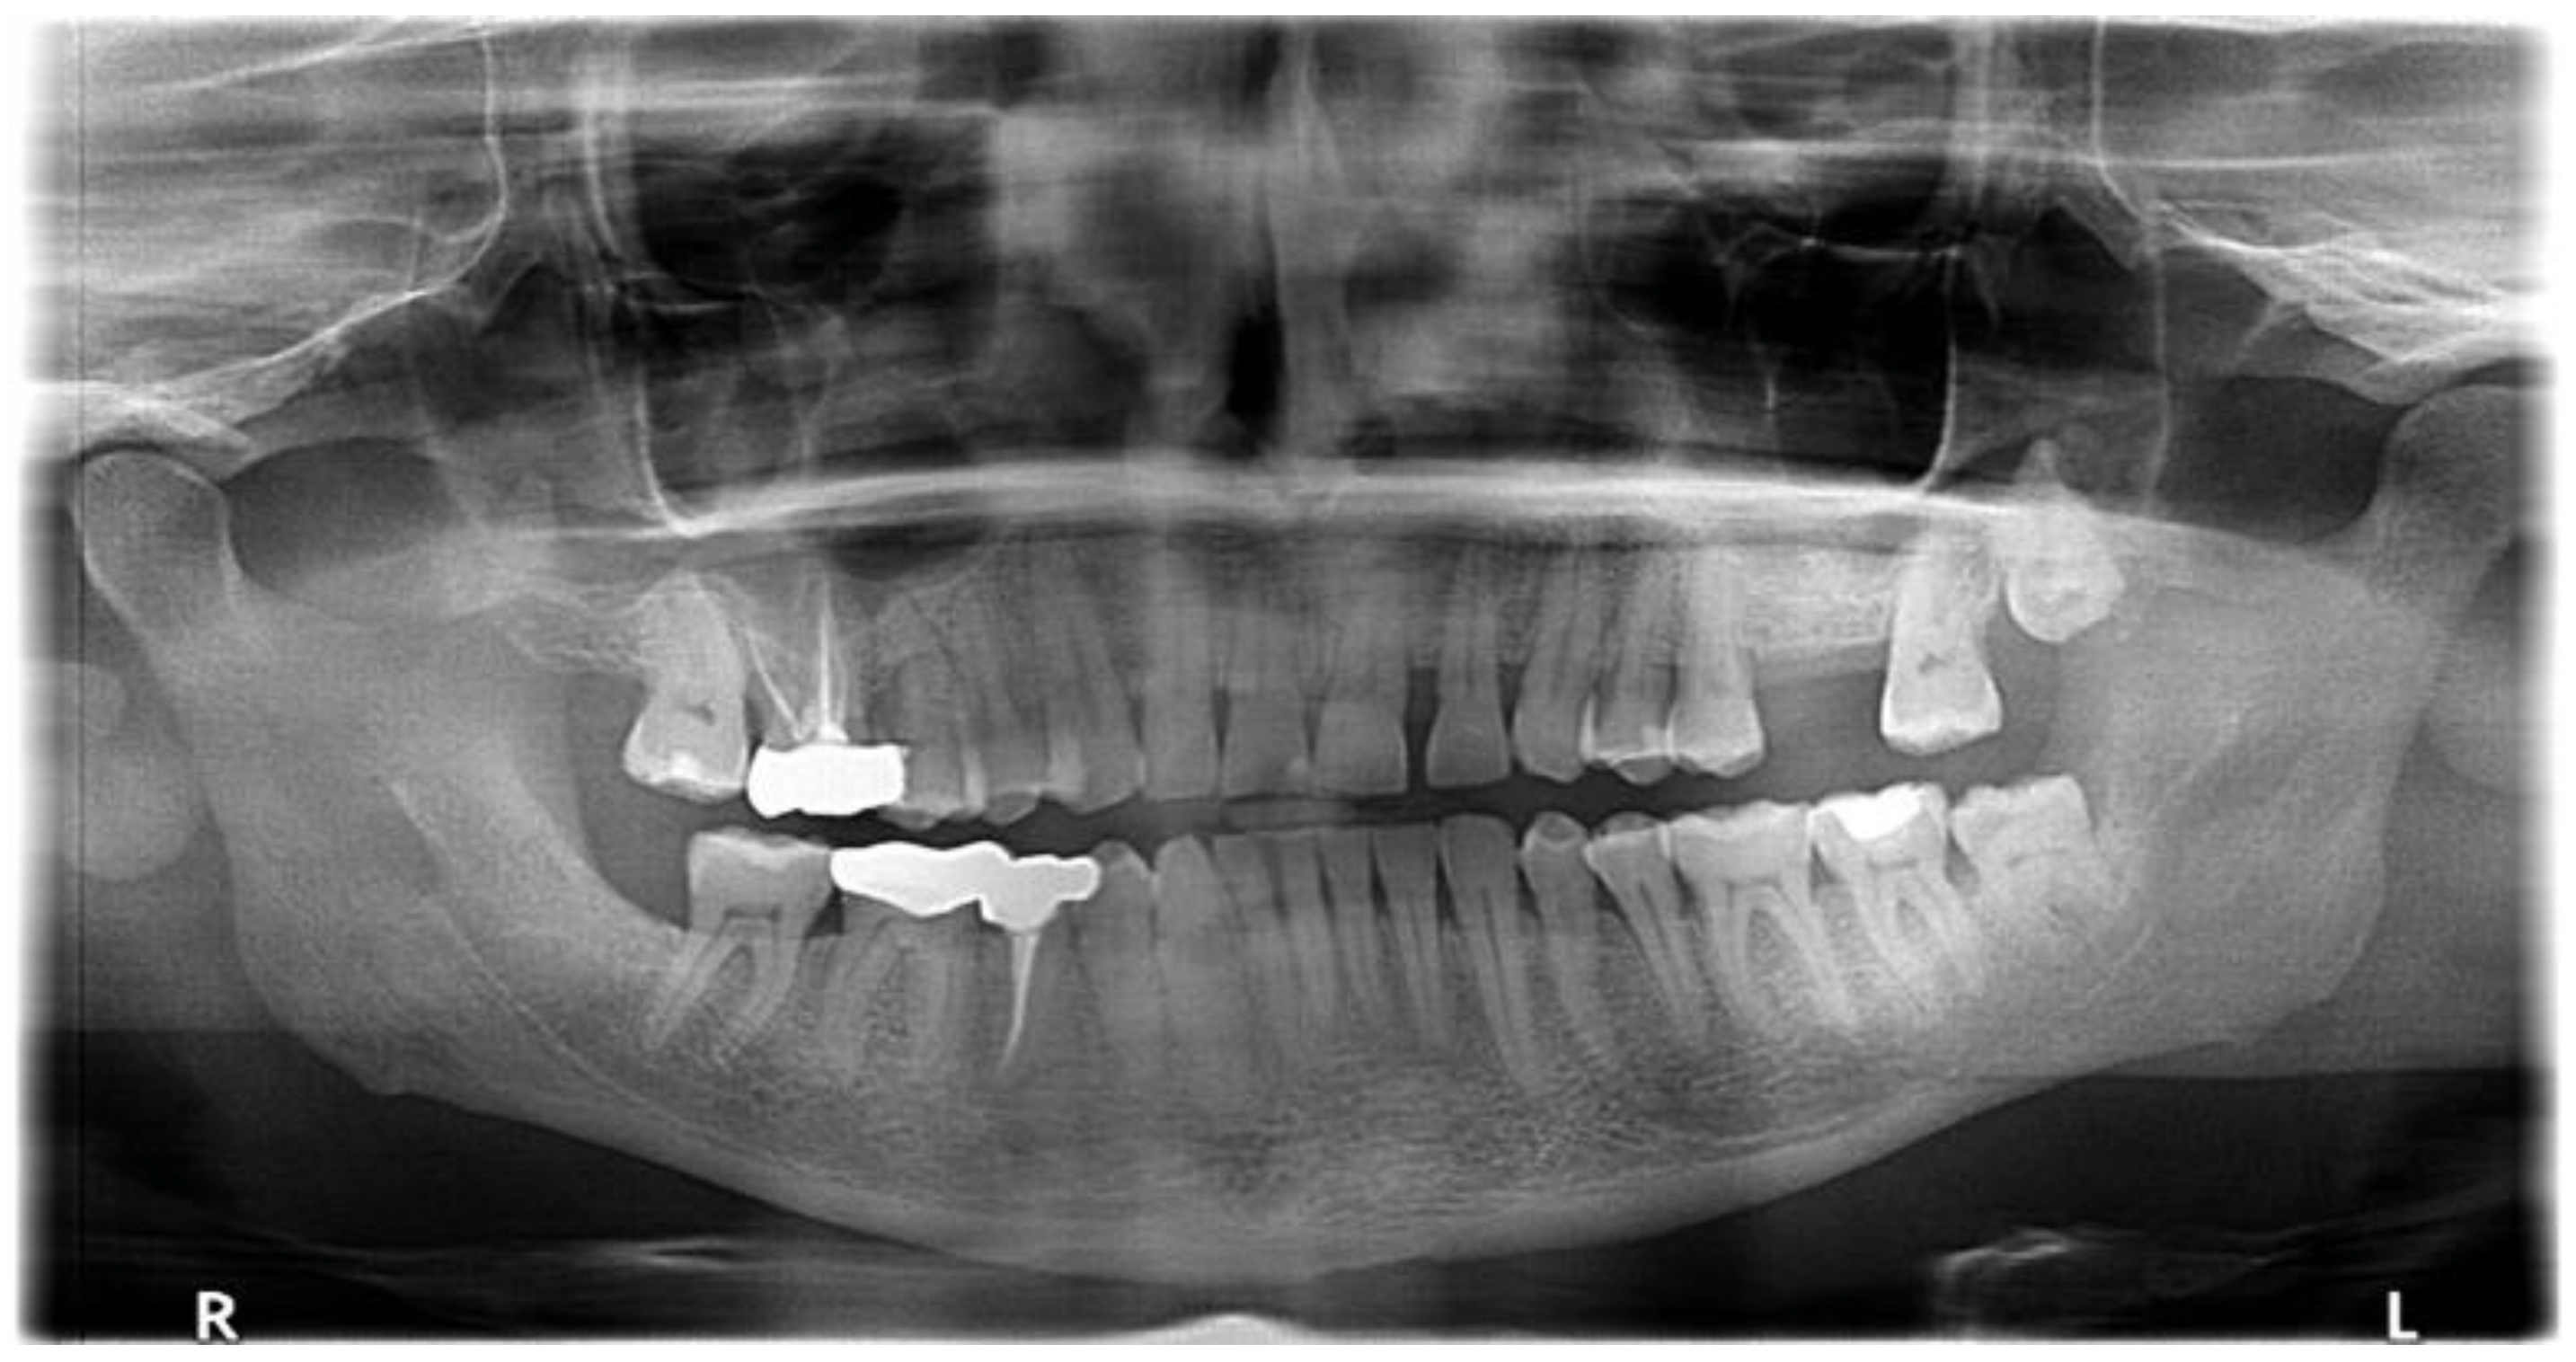

3.3. Case 3: Severe Pericoronitis